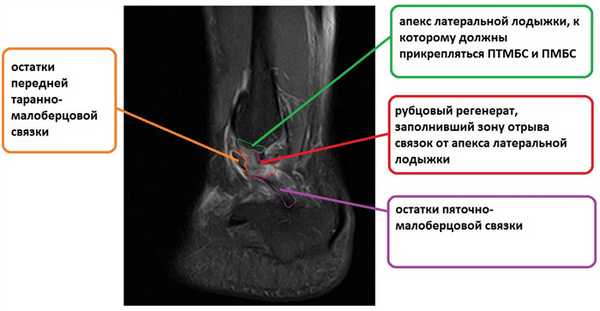

На этом этапе пациентка лечилась по стандартному сценарию «растяжение голеностопа». Носила ортез, мазала голеностоп вольтареном и лиотоном, разгружала его при помощи трости. Но в связи с длительно сохраняющимся болевым синдромом было выполнено МРТ, при котором диагностирован застарелый разрыв передней таранно-малоберцовой связки, пяточно-малоберцовой связки правого голеностопного сустава, контузионное повреждение латеральных отделов таранной кости.